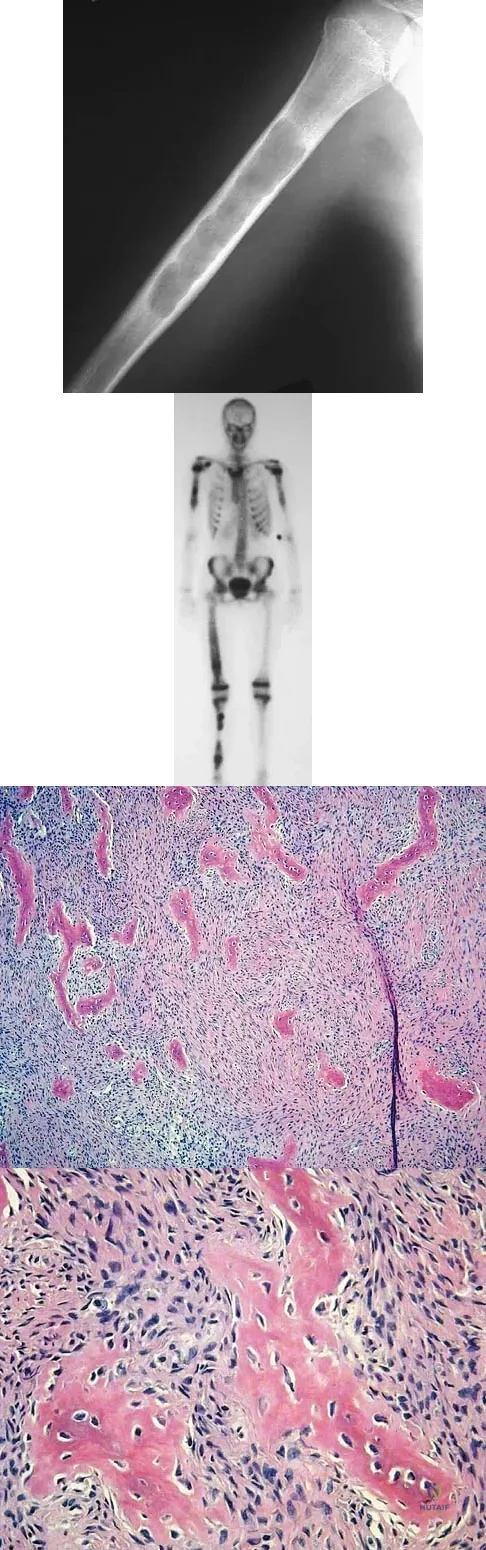

A 10-year-old girl reports activity-related bilateral arm pain. Examination reveals no soft-tissue masses in either arm, and she has full painless range of motion in both shoulders and elbows. The radiograph and bone scan are shown in Figures 20a and 20b, and biopsy specimens are shown in Figures 20c and 20d. What is the most likely diagnosis?

Detailed Explanation